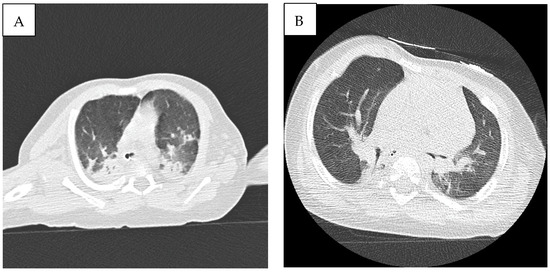

2. Case Description